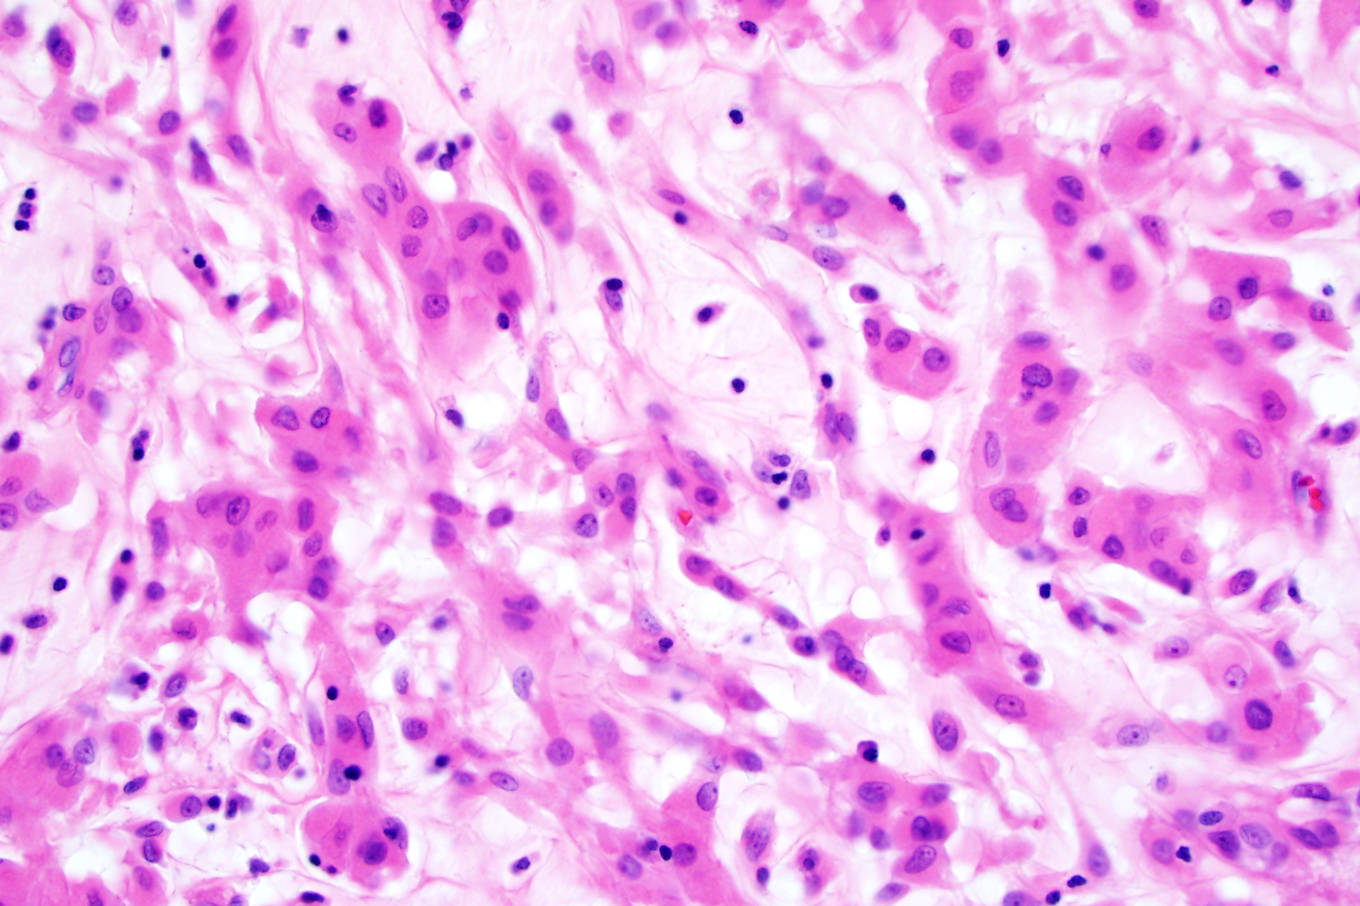

Using tumor genome sequencing, Solomon identified the first potential targeted drug to treat chordoid gliomas, a rare type of brain cancer that develops within the third ventricle, a fluid-filled pocket that helps cushion the brain. Although these tumors are slow-growing, their proximity to the hypothalamus – a critical brain region involved in hormone production – makes chordoid gliomas difficult and potentially deadly to remove.

In the study, published on Feb. 23, 2018, in Nature Communications, Solomon’s team sequenced the genomes of 13 chordoid glioma tumors and identified a single mutation in one gene, PRKCA, that was consistent across all 13 samples. PRKCA is part of a key growth pathway, called MAP kinase, that is turned off in normal brain cells. The mutation in PRKCA activates this MAP kinase pathway, causing the cells to divide dangerously and form a tumor.